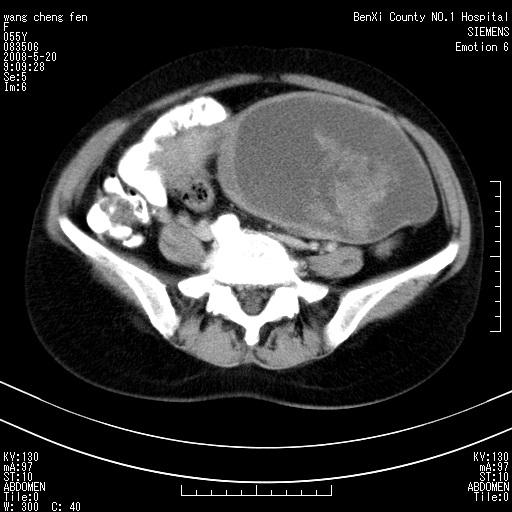

女、绝经后阴道流血3个月

左侧附件区巨大囊实性病灶,边缘光整,病灶囊壁较厚,增强示囊壁及实性部分明显强化,强化呈度与宫体实质大致相同,宫腔积液征像,未见盆腔积液等其他异常,考虑左侧卵巢囊腺癌,不除外囊腺瘤及浆膜下肌瘤坏死

左侧附件区巨大囊实性病灶,边缘光整,病灶囊壁较厚,增强示囊壁及实性部分明显强化,强化呈度与宫体实质大致相同,宫腔积液征像,未见盆腔积液等其他异常。绝经后阴道流血3个月,结合病史左侧卵巢囊腺癌首先考虑,宫腔扩大不除外累及。期待结果。

支持浆膜下子宫肌瘤.之前由于网络原因未看全图片,现在重看,宫颈见一类圆形低密度影,增强轻度强化,低于肌层强化,宫腔扩大,考虑宫颈癌伴宫腔积液可能性大.

1,宫颈部占位,宫颈癌?2,左侧附件区囊实性占位,界较清,实质部分强化明显。考虑浆膜下或阔韧带肌瘤囊变可能大。囊腺类肿瘤不除外。